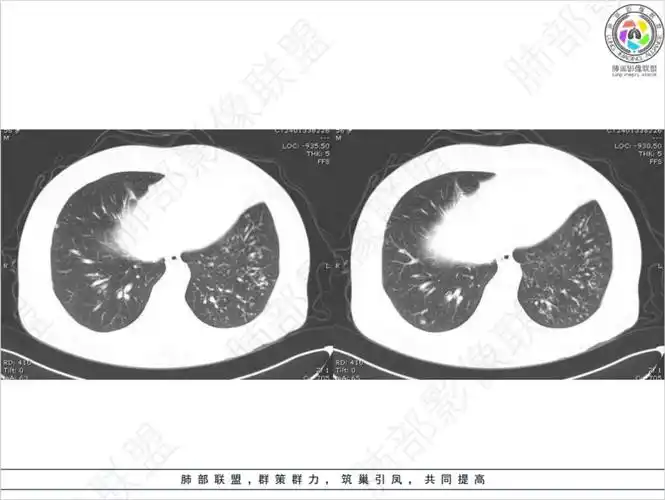

胸部学组:肺弥漫性小结节影

肺结核的ct影像表现特点多样且复杂:

病灶多灶性,多态性,这个病例如何确诊肺结核?